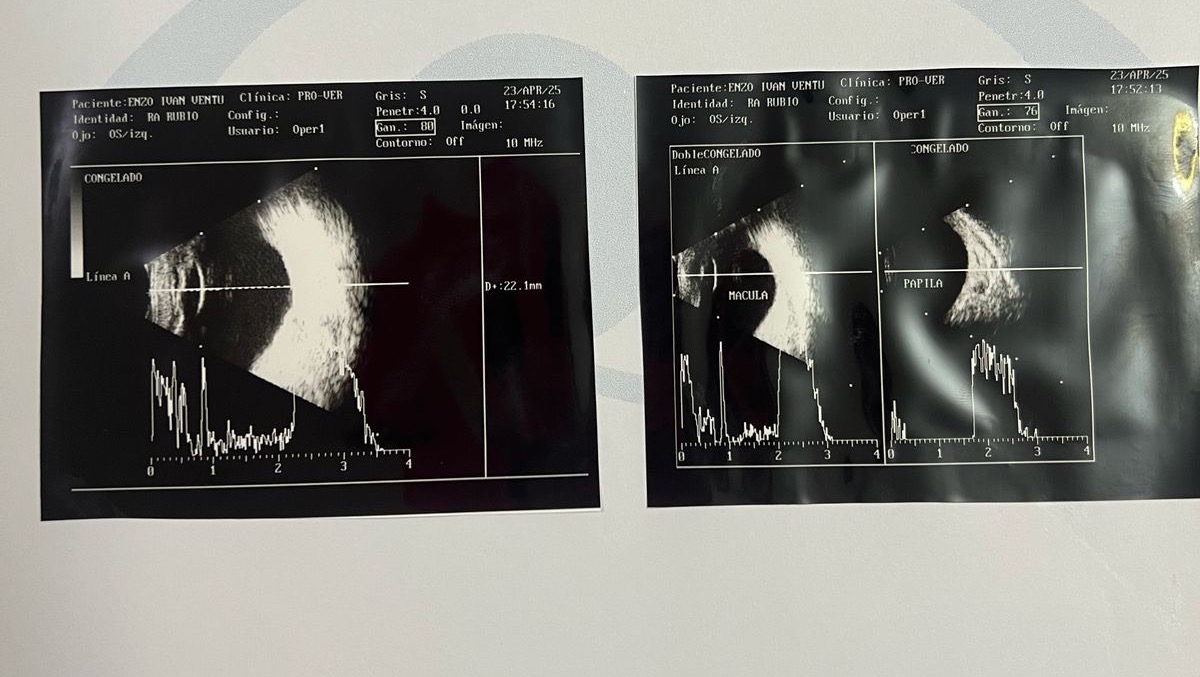

*Enzo’s Fight to See the World*

Enzo is our baby boy, just 1 year and 10 months old, and he has already gone through 7 major eye surgeries in his short life.

He was born with a rare condition called bilateral coloboma of the upper eyelids, which severely affects his ability to see and protect his eyes.

7. Emergency scleral graft surgery - Doctors discovered a damaged cornea and had to urgently place a scleral graft to protect the eye and prevent a possible retinal detachment.

What’s Next: A Keratoprosthesis (Artificial Cornea)

Enzo still cannot see, but there’s hope.

Due to the severity of his condition and the damage to his cornea, doctors have recommended a keratoprosthesis — an artificial cornea implant.

This is not a standard corneal transplant, but a much more complex and delicate procedure that is only performed in specialized medical centers.